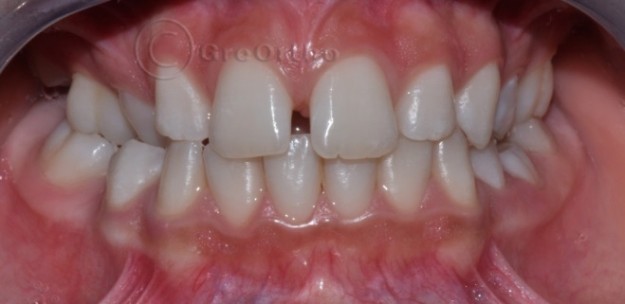

Лечение на свръхбройни зъби и ретенирани зъби Увеличеният брой зъби извън нормалния набор за човека (32 в постоянно съзъбие и съответно 20 за временно съзъбие) наричаме хиперодонтия. Те се формират и залагат от зъбната ламина, чрез разцепване на две и развитие на два зародиша. Свръхброините зъби могат да причинят различни нарушения, включително персистиране на временните…